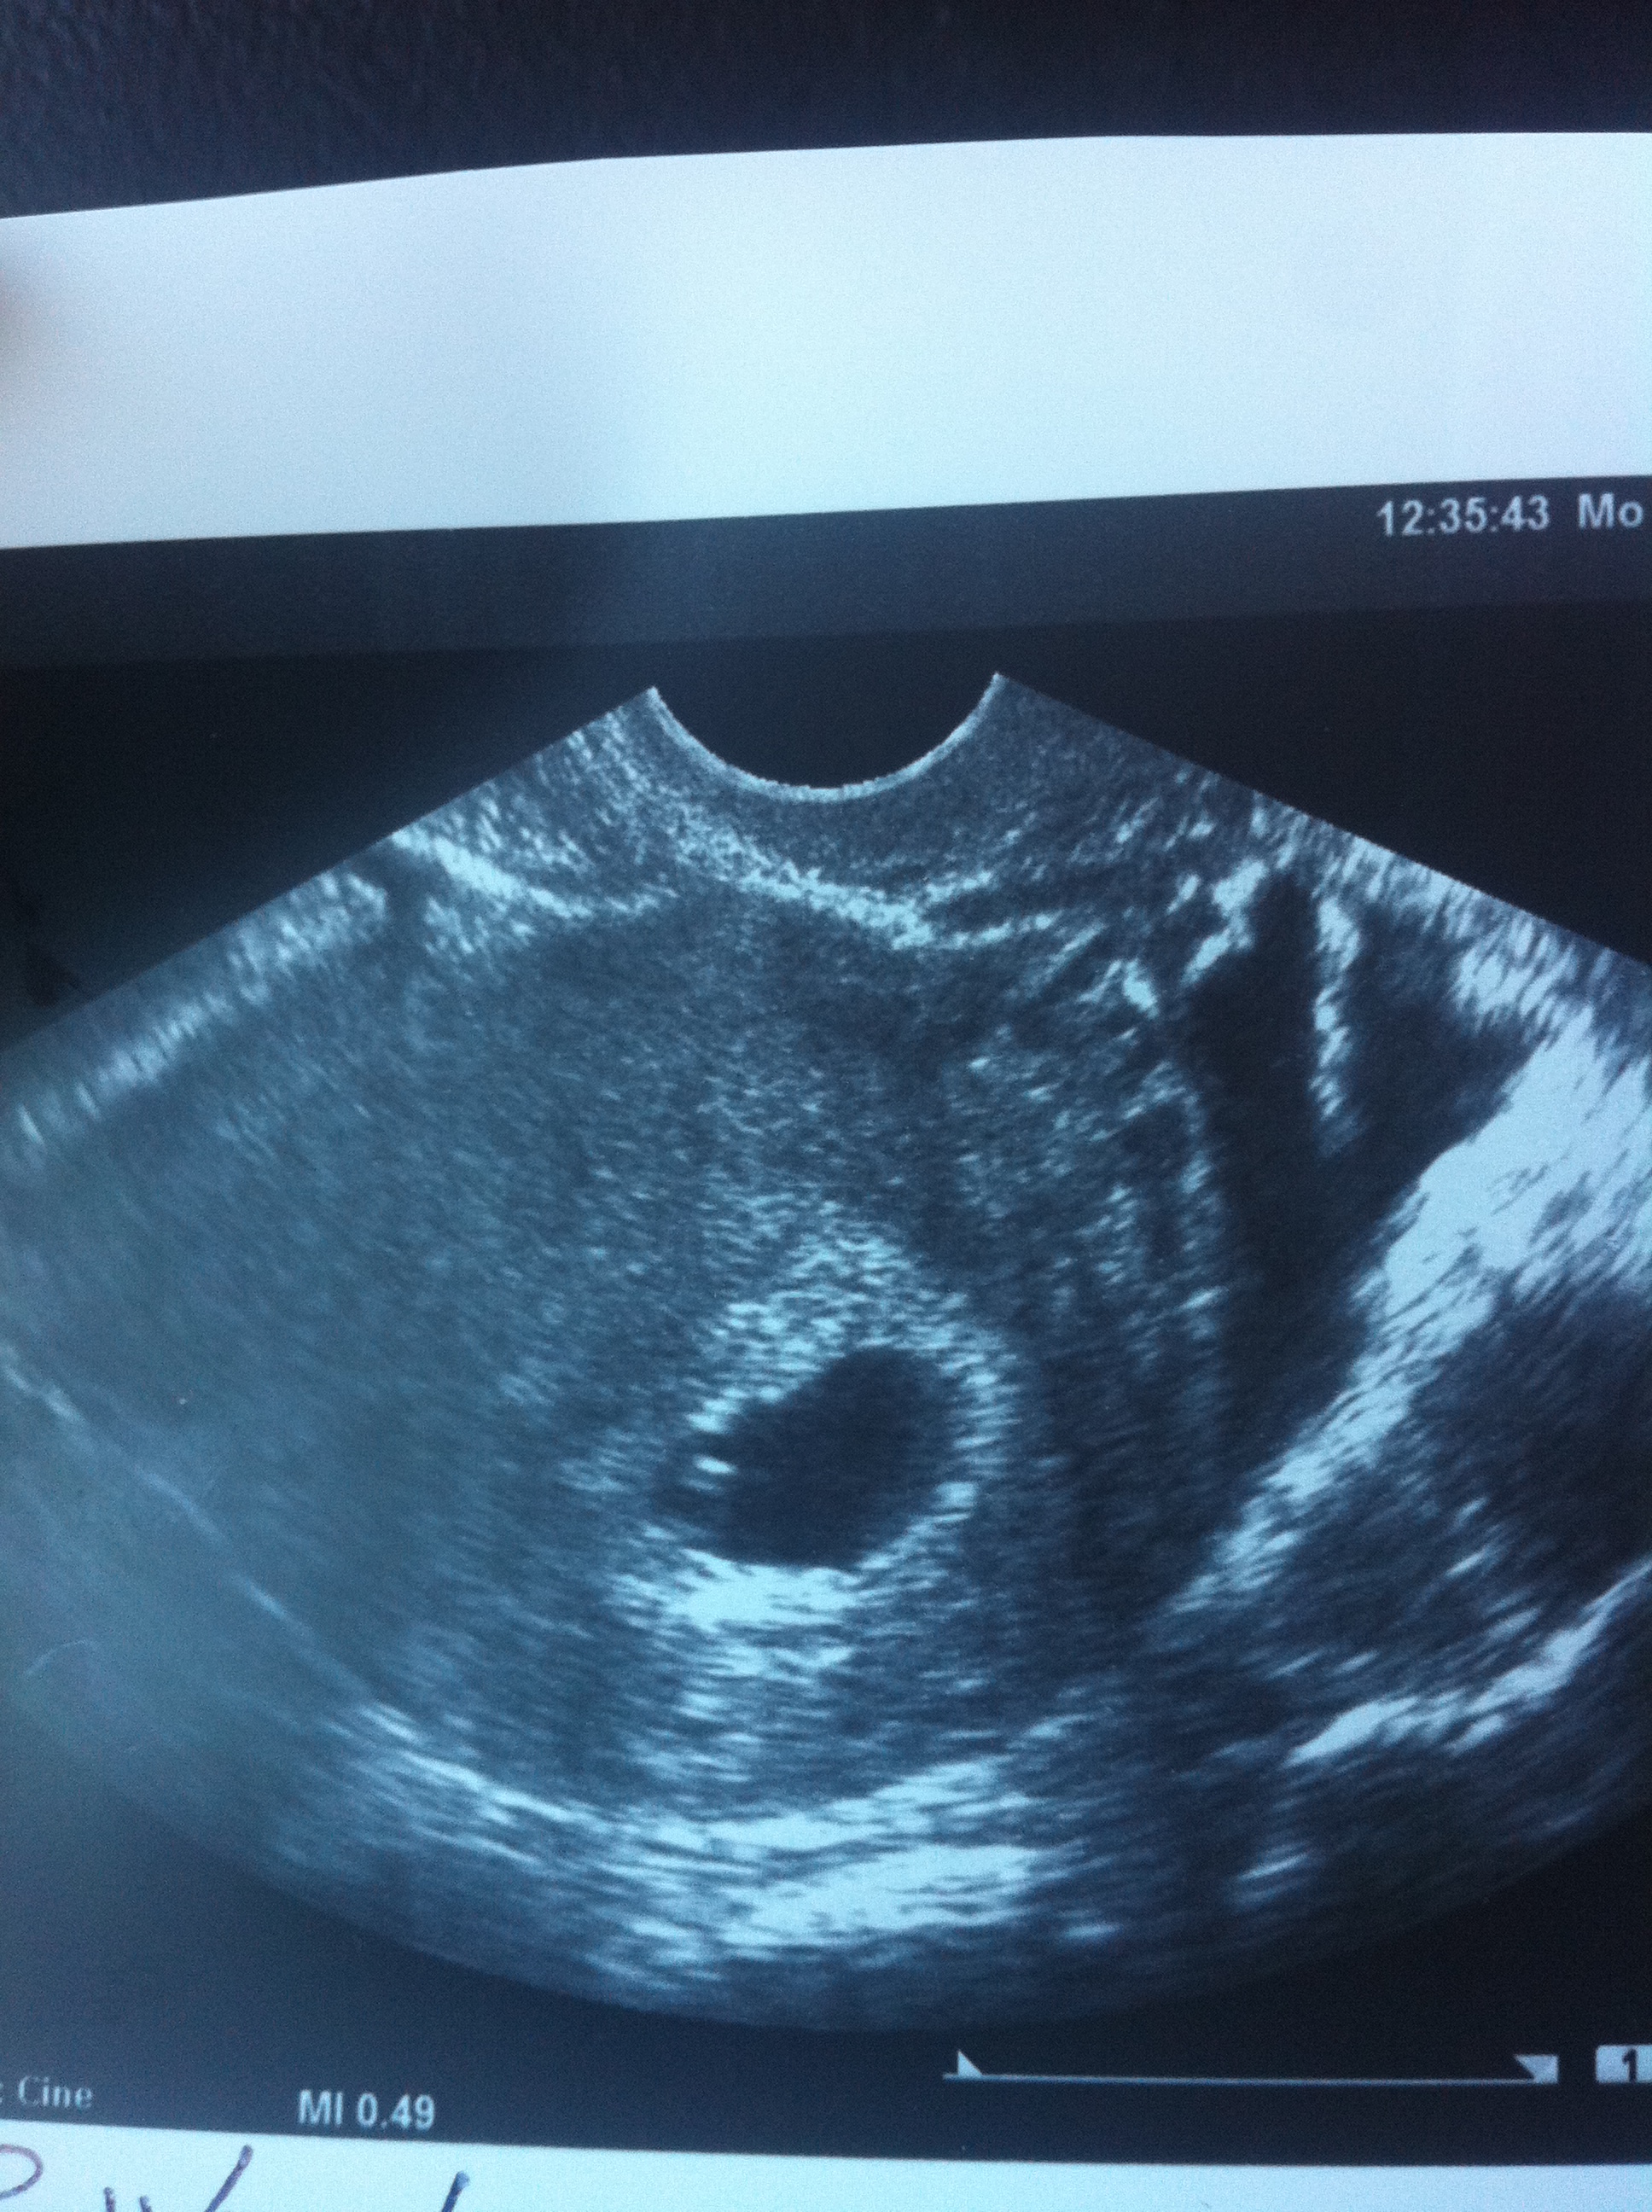

Dr Ramzi himself predicted a boy for me based on my 6 week ultrasound, attached here Attachment 16468

I then sent him my 7 1/2 week ultrasound and he changed his prediction to girl now, see the difference, the placenta has spread out more to the left now.

Attachment 16466

Gah, the post won't let me delete the 6 week ultrasound pic that I had sent to him labeled (below), where I thought the placenta was forming is not accurate, my placenta is forming anterior not posterior so it is above and not below where I outline.